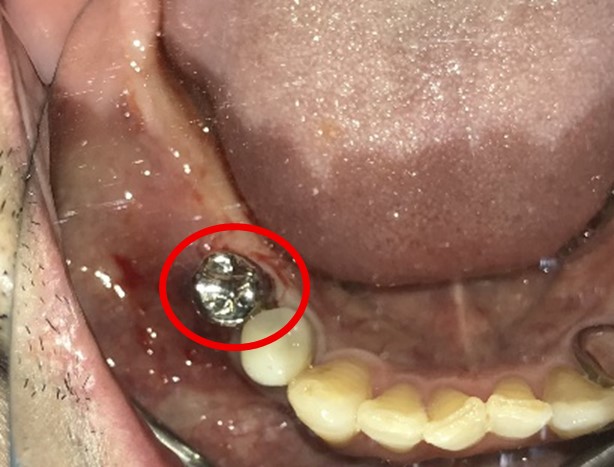

Before

※赤丸を抜歯しました。

After